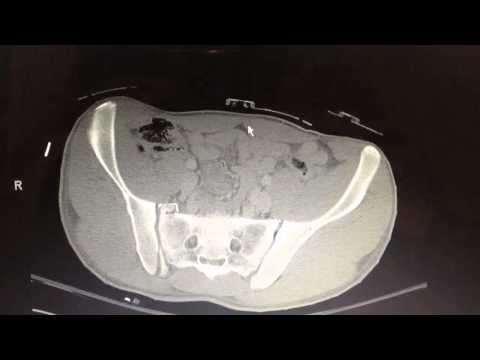

Axial CT scan of pelvic ring injury

1) Does this show a pelvic ring injury?